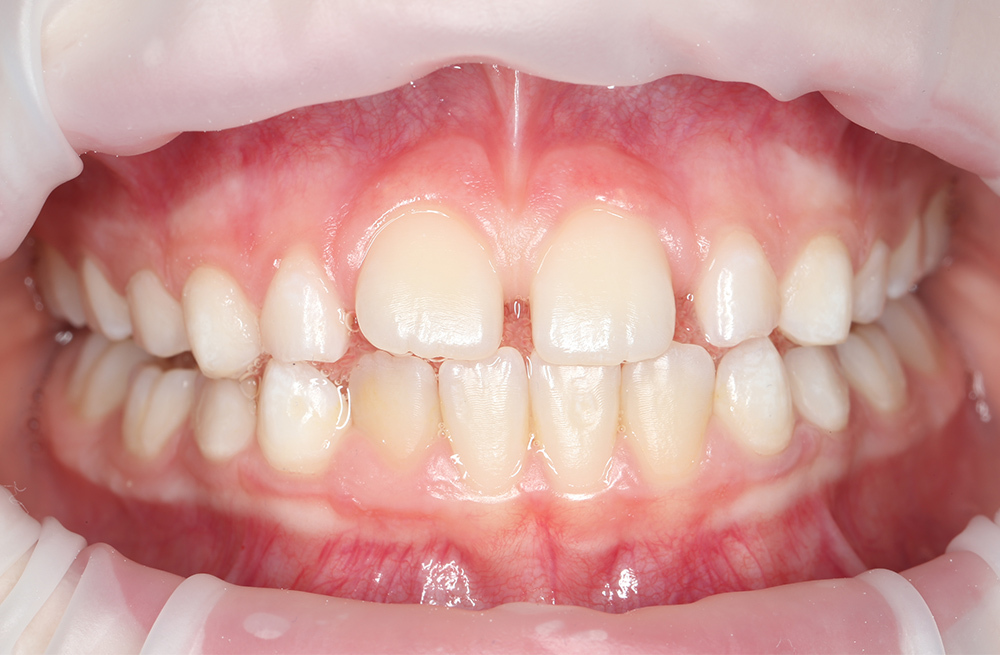

Своевременное лечение кариеса постоянного зуба у подростка без жалоб